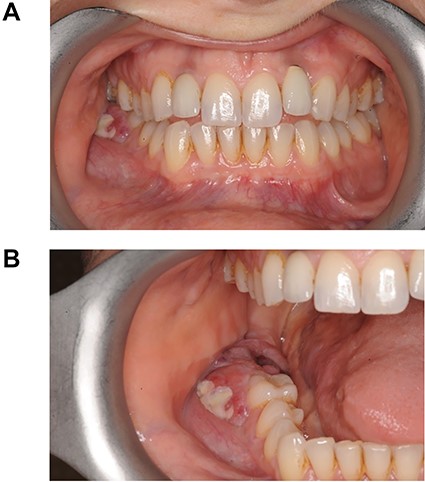

A 37-year-old fit and well lady presented to her General Dental Practitioner (GDP) complaining of pain in the right side of her mandible and episodic numbness in the ipsilateral mental nerve distribution. An orthopantomogram (OPG) (Fig. 1) was taken, with the GDP contentiously identifying an area of increased radiolucency at the apex of the right lower second molar. The patient was referred to a specialist dentist for root canal treatment of the tooth, with the GDP suspecting irreversible pulpitis.

OPG taken on patient’s first visit to GDP. Demonstrates radiolucency at apex of LR7.